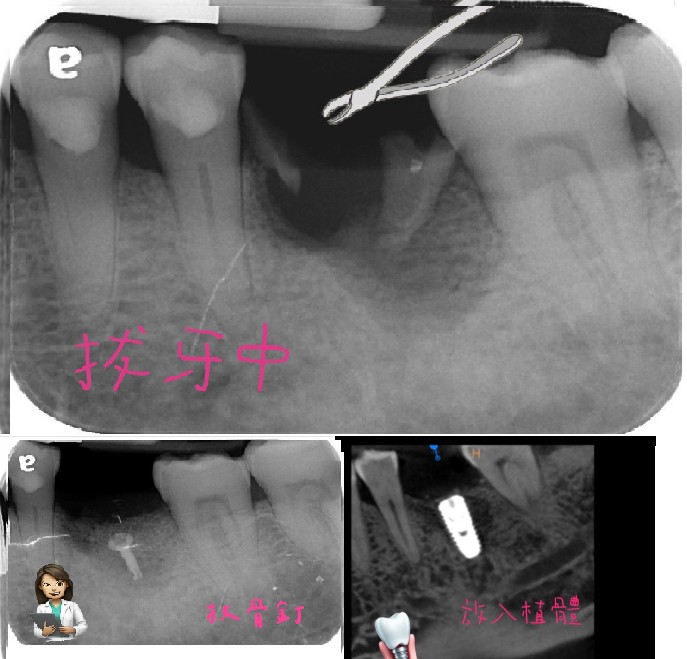

前段期間簡醫師接到了一名患者,H先生

來的時候我們發現牙周狀況真的不是很好,上顎的左上其中兩顆牙,周圍基底幾乎掏空;沒有了骨頭!可想而知,牙齒君們是搖搖欲墜的狀態。

醫師和患者討論了治療計劃以後,決定先做拔牙的部份。

在拔牙的同時,我們一併做了ARP,也就是齒槽骨保存術。在拔牙後填入填入骨粉和覆蓋生物膜,以防止齒槽骨萎縮、以利其生長,為將來植牙創造更好的條件,畢竟要在上面蓋房子,也要打造良好的地基對吧?

在術後的9個月,執行了植牙手術,由於患者本身的自我條件較不足,在手術的同時,還是一起進行了鼻竇增高術:

這也是補骨的一種,解決上顎植牙時因骨頭不足的問題,往上推高鼻竇底部的黏膜,在撐出的空間填入骨粉,以增加骨頭高度和密度,來確保植體有足夠點去支撐,藉此提升植牙成功率,以避免植體穿破鼻竇膜造成鼻竇炎。

而後雖然手術順利完成,但醫師還是擔心患者在植牙的後方,也有一顆出現牙周問題的牙齒,會去影響前方的植牙,不過目前還是可再觀察的。需請患者注意定時回診,以及進行植牙的定期保養才行。